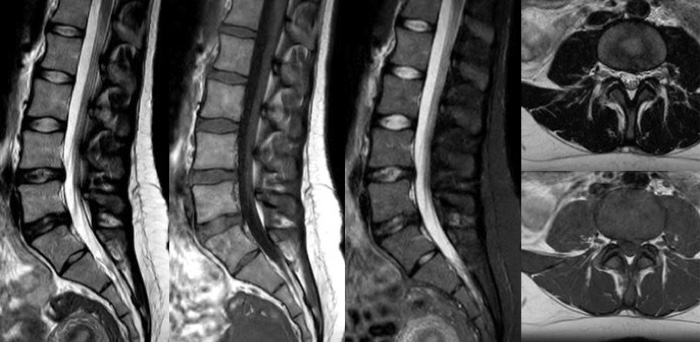

時間を味方につける - Compressed SENSEを使用すると、実質的に同等の画質を保ちつつ、撮像時間を最大50%²短縮できます。空間分解能が60%向上した高品質のMR画像を得ることで確実な診断が可能になります。

Conventional

Compressed SENSE